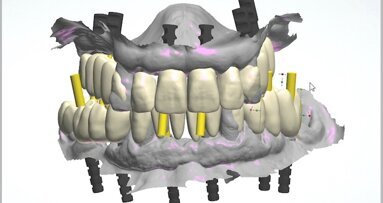

The collected data, along with preliminary plans for potential implant receptor sites (Blue Sky Plan, Blue Sky Bio), was submitted to the laboratory (ROE Dental Laboratory) for review. The 3D data from the CBCT scan was then merged with the IOS data set to aid in determining a restoratively driven solution for both arches. The laboratory then designed provisional full-arch screw-retained restorations utilising CAD software at the designated VDO required for the prostheses. The desired tooth position as visualised with the 3D reconstructed volume of bone helped to determine the most favourable implant receptor sites. A virtual remote planning session was held with the laboratory to finalise the full-template guided surgical plan (CHROME GuidedSMILE, ROE Dental Laboratory), which incorporated a 2 mm increase in the VDO, and the case was sent for production. The CHROME GuidedSMILE protocol consists of several component parts, which provide a stackable solution with metallic scaffolding to control the bone reduction, the preparation of the osteotomies, full-template guidance of the implants into the bone, control of implant depth, trajectory and rotational indexing, the positioning of the MUAs and the delivery of the provisional restorations.1

After four months, the patient returned to complete the process of finalising the final prostheses. Final records were taken, including new digital scans and photographs. Photographs included the patient profile when smiling and not smiling as well as intra-oral occlusion. The digital scans included a facial scan acquired from the CBCT device, maxillary and mandibular soft-tissue scans using scan bodies (DESS), bite registration, an iJIG scan of the provisional restorations for tooth positions,3 photogrammetry (iCam4D, iMetric 4D) and Grammetry scans (Fig. 15). The Grammetry scans were scanned extra-orally with both the intra-oral scanner and an extra-oral desktop scanner (Medit T710) for comparison.